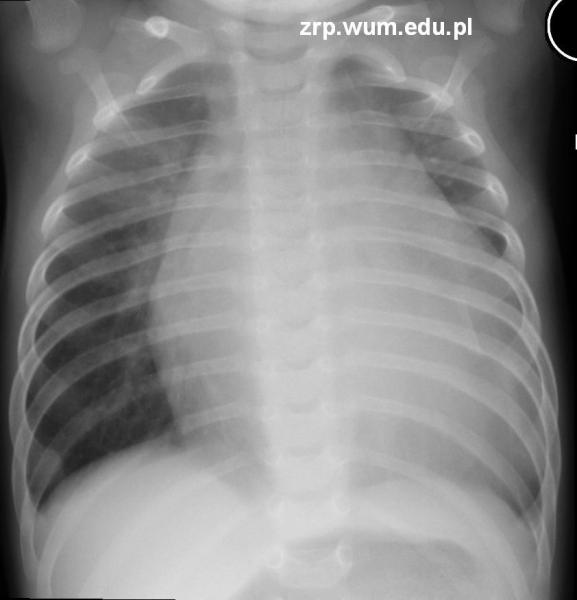

Przypadek 25: 4-miesięczny pacjent przyjęty do diagnostyki braku przyrostu masy ciała, z nieprawidłowym zapisem EKG i cichymi tonami serca.

Rozpoznanie: W badaniu RTG klatki piersiowej stwierdzono znaczne powiększenie całej sylwetki serca (wskaźnik sercowo-płucny 0,75).

Pytanie: Kiedy mówimy o powiększeniu sylwetki serca? Wymień przyczyny powiększenia sylwetki serca u dzieci.